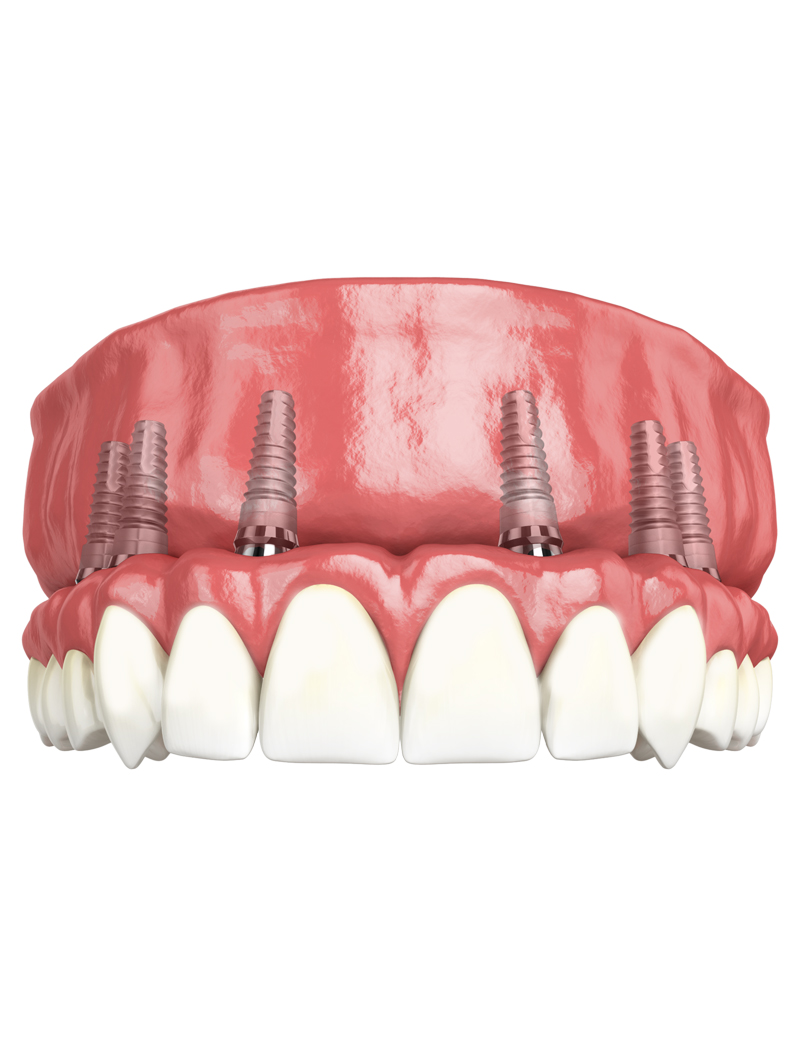

Implantology All on 8

The All on 8 dental implant system consists of positioning 8 dental implants per dental arch, functioning as "anchors" for a fixed and non-removable dental bridge. This system is recommended in cases where the patient has lost more than 80% of his natural teeth.

These dental implants will support a fixed dental bridge (permanently cemented on the implants) between 12 and 14 units (teeth). Before receiving All-on-8, the patient must have enough bone to support the implants. If there is not enough bone, a bone graft is needed. An All-on-8 requires more bone and more bone strength than an All-on-4.